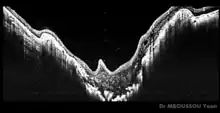

Le syndrome de la fleur de liseron ou anomalie de Handmann est une anomalie congénitale de type neuropathie de la papille optique, de manière généralement unilatérale ou plus rarement bilatérale. Ce syndrome entraîne une diminution de l'acuité visuelle et une amblyopie variables en fonction du degré avec lequel sont touchées les fibres optiques. Il peut être associé à d'autres affections, comme une atteinte du système nerveux central, des anomalies des systèmes endocrinien, rénal ou respiratoire, un bec de lièvre, une fente palatine par exemple.

Dans le syndrome du liseron, la papille forme une sorte d'excavation en entonnoir. Celle-ci est occupée par une masse de tissu glial plus ou moins importante, d'un anneau pigmenté péripapillaire, et les vaisseaux sont organisés selon une disposition radiaire[2]. Plusieurs formes cliniques existent[2].